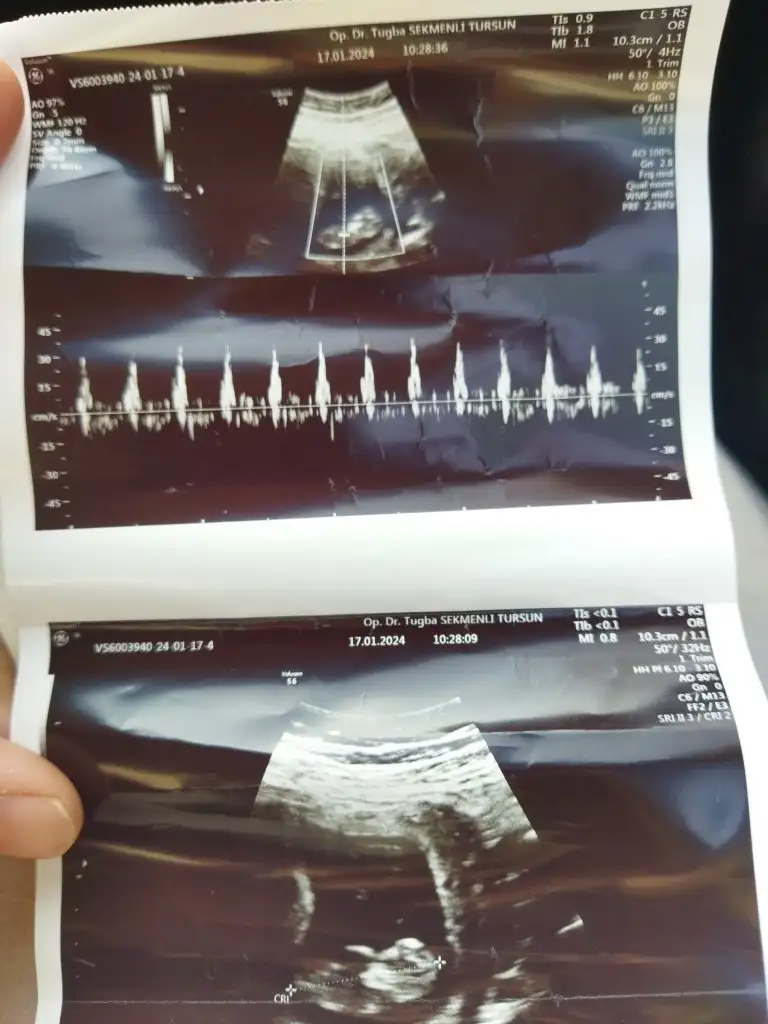

Sizce nedir cinsiyet kızlar 🥰 11+2

Eklentiler

• IMG_20240117_105712.webp

IMG_20240117_105712.webp

36,7 KB · Görüntüleme: 248